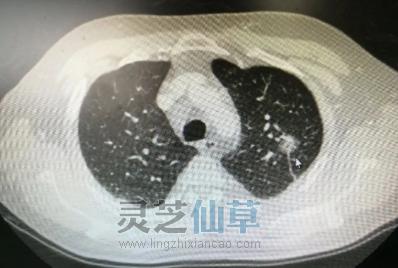

灵芝孢子油对肺结节的调理作用

什么是肺结节?肺结节是指肺部影像上各种大小、边缘清楚或者模糊、直径小于等于3cm的局灶性圆形致密影。现多数人认为细胞免疫功能和体液免疫功能紊乱是结节病的重要发病机制。临床表现胸内结节病早期常无明显症状和体[详细]